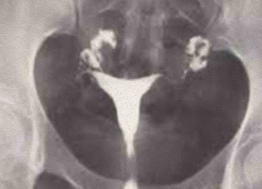

HSG Útero Bicorno: Dois cornos uterinos com indentação externa profunda (>1 cm).

• Útero Bicorno: Dois cornos uterinos com indentação externa profunda (>1 cm).

HSG Útero Septado: Septo mediano dividindo a cavidade, com contorno externo uterino normal (convexo).

• Útero Septado: Septo mediano dividindo a cavidade, com contorno externo uterino normal (convexo).